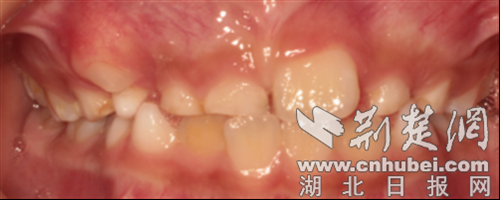

它的“存在感”可强可弱:有的多生牙会像正常牙齿一样萌出,肉眼就能看到;有的则一直埋伏在颌骨内,只有拍X光片(如口腔CT)时才会被发现。从形态上看,它也很“任性”——可能是正常的牙齿形状,也可能是畸形的小颗粒,颜色、大小都与正常牙齿有明显差异。

引发口腔疾病:多生牙与正常牙齿之间容易藏食物残渣,刷牙难以清洁,长期下来可能诱发龋齿(蛀牙)、牙龈炎,出现牙龈红肿、出血、口臭等问题。

日常观察:家长可以定期查看孩子牙齿,若发现恒牙萌出后乳牙未脱落、牙齿排列明显拥挤,或口腔内有“额外冒出的小牙齿”,需警惕多生牙。